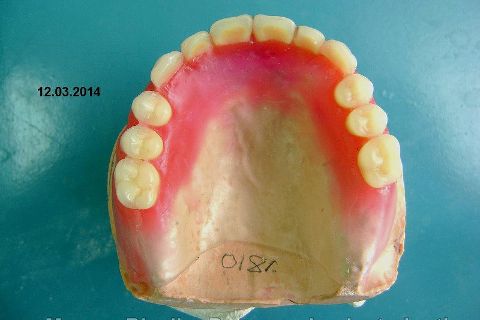

FASE PROTÉTICA DA REABILITAÇÃO EM MAXILA ATRÓFICA...incluindo a reabertura, instalação dos minipilares e PTR provisória reembasada sobre os cilindros de proteção.